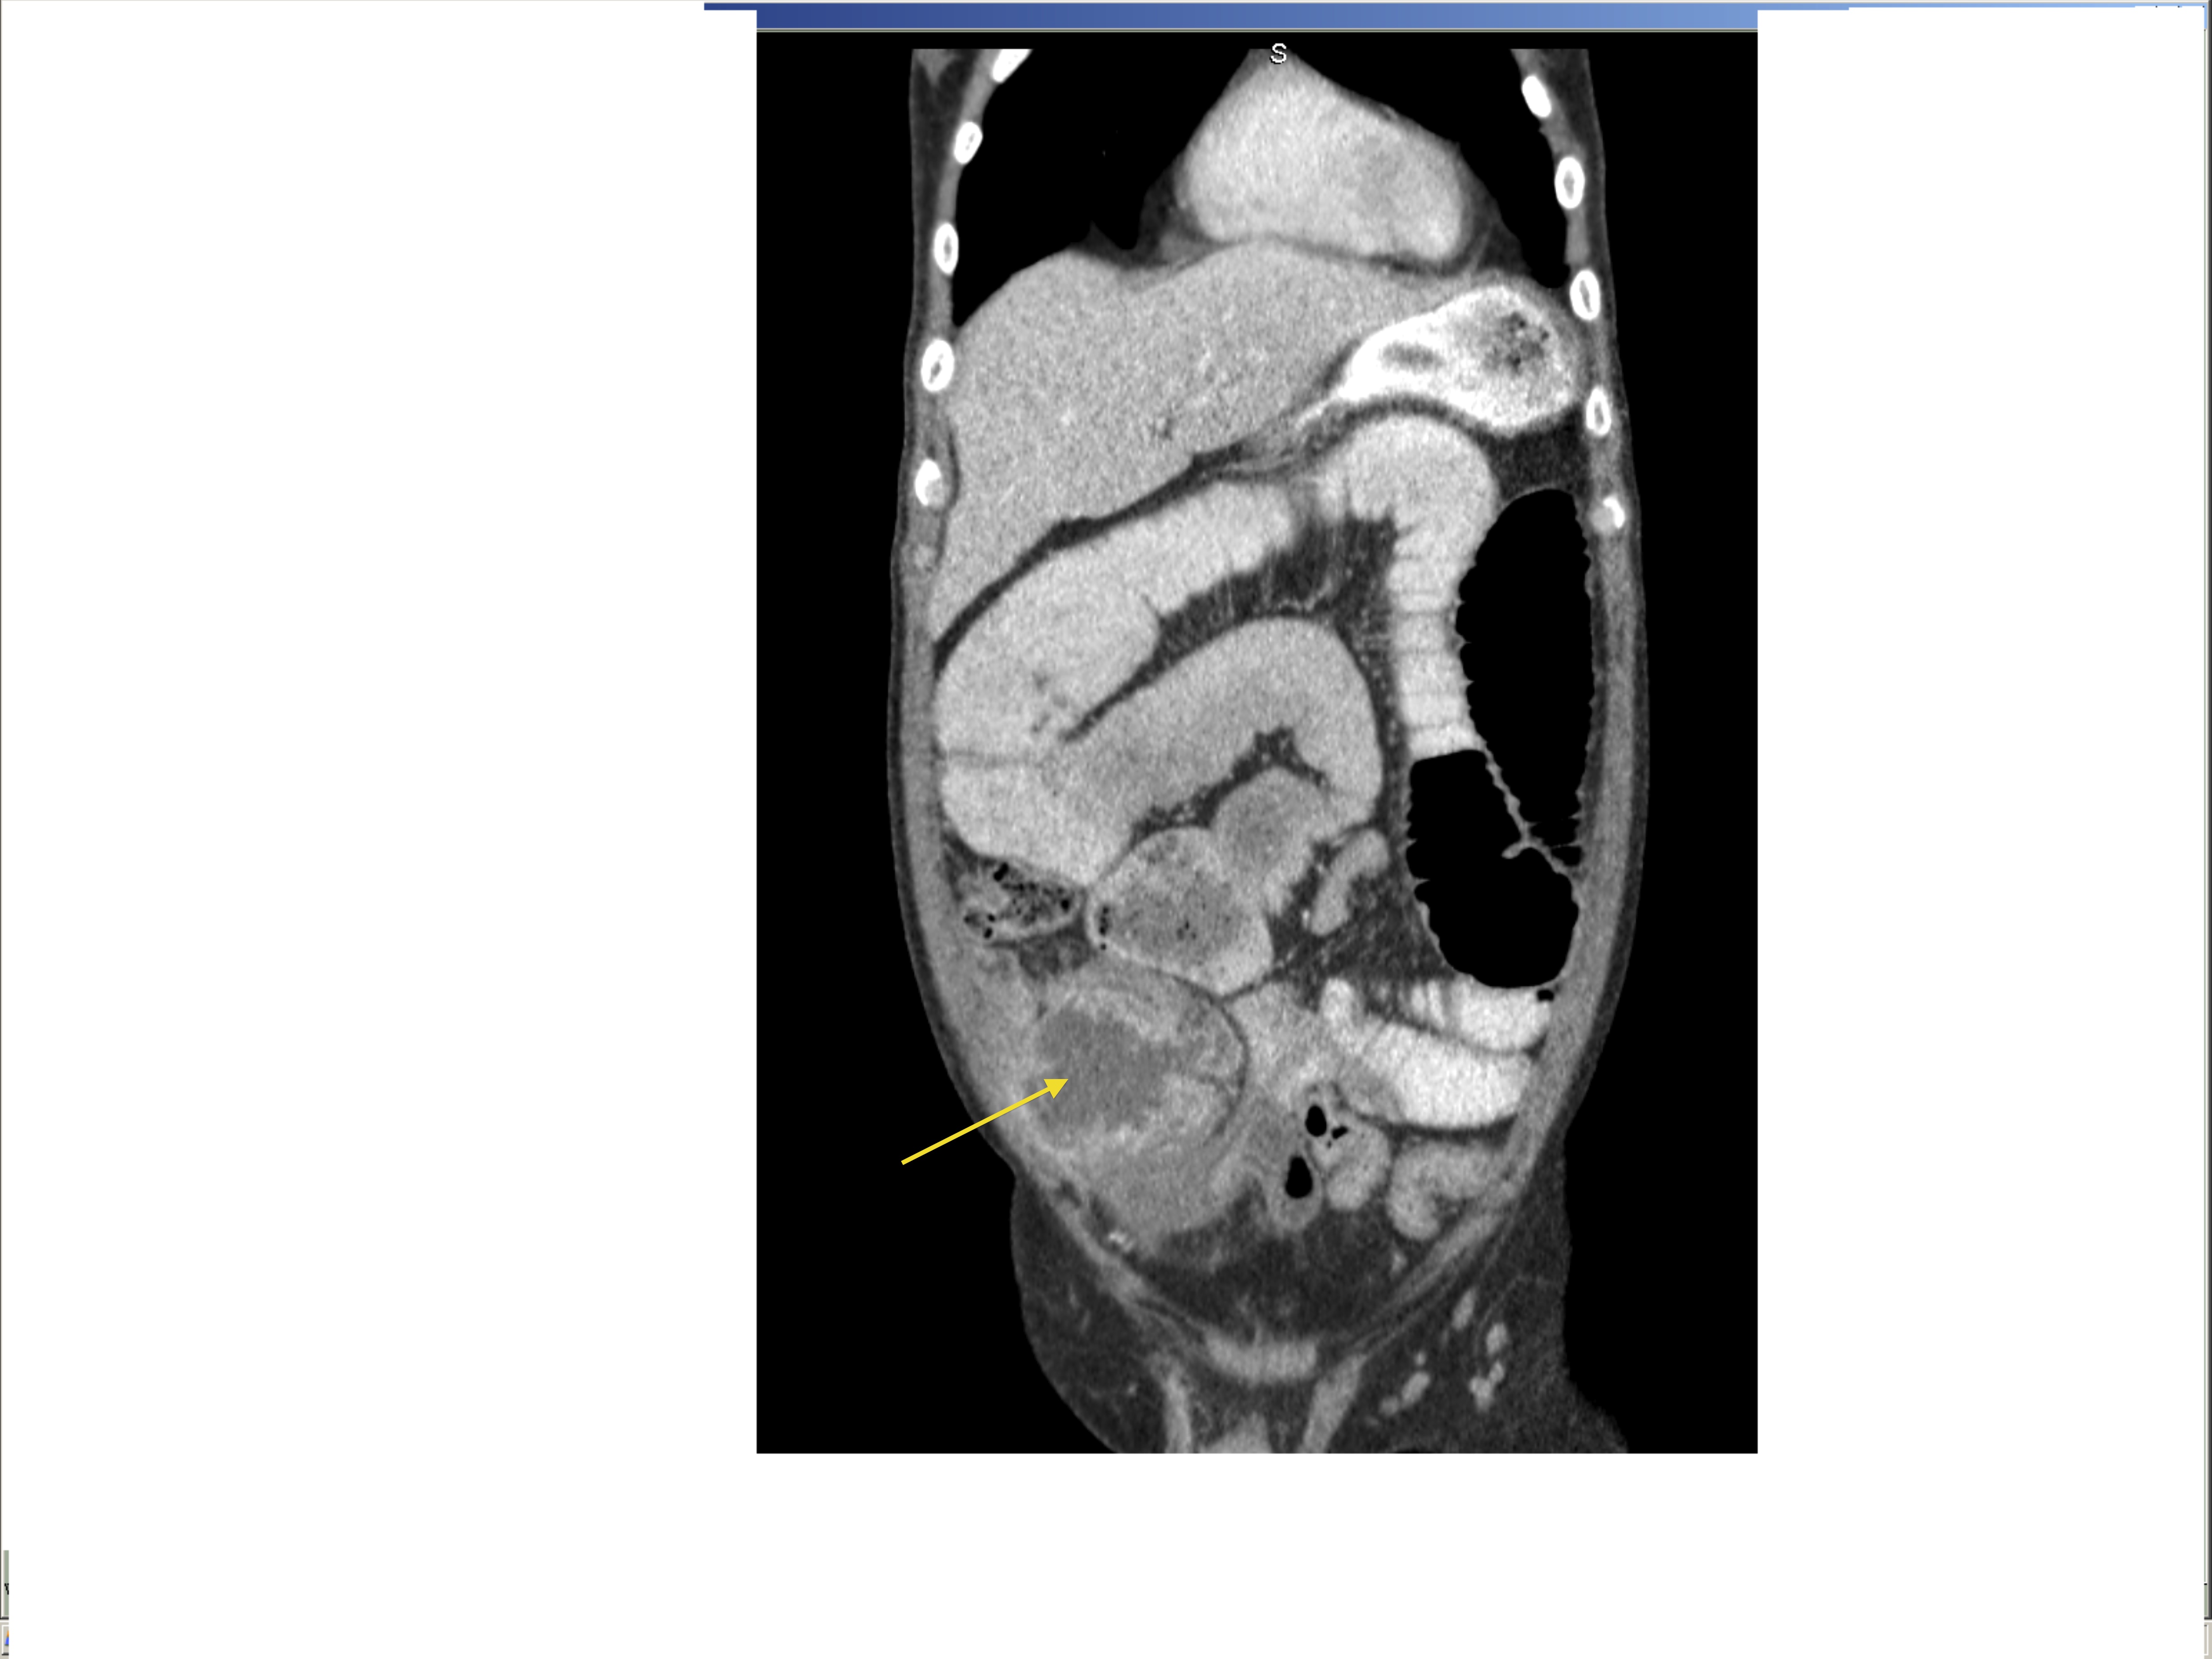

Small bowel obstruction is a common clinical presentation that presents a diagnostic conundrum. Over the last 2 decades, there has been a paradigm shift in the radiological investigation of small bowel obstruction (SBO) and in the indication for and timing of surgical intervention. Cross sectional imaging (predominantly computed tomography) has largely replaced the widespread use of radiographic small bowel follow-through studies as the imaging modality of choice for SBO. This article illustrates the current imaging modalities available for diagnosis of small bowel obstruction. (Full text available online at www.medpharm.tandfonline.com/ojfp) S Afr Fam Pract 2015; DOI: /10.1080/20786190.2014.977052